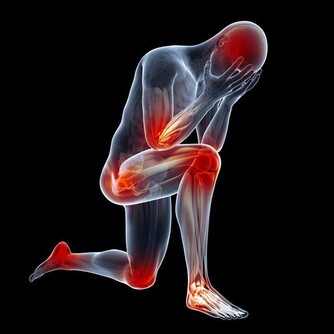

當血管阻塞情況加重,就會出現一種奇怪的狀況——間歇性跛行。

比如有些老人家,走了2站路就感覺走不動了,腿酸痛,休息一會,又能走了是典型的血管動脈阻塞的癥狀,血管性性間歇性跛行。

這種酸痛,不是來源於關節疾病,而是源自肌肉酸痛,主要就是因為肌肉運動需要耗氧量大,而血管沒有及時供給造成的酸痛。